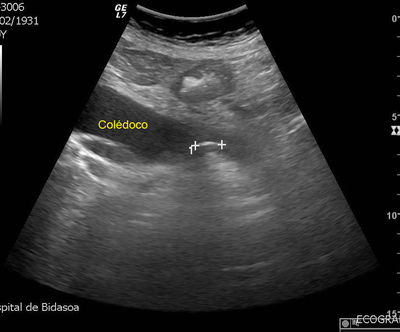

Question 9

Question

Una mujer de 49 años acude de Urgencias por presentar tiritona, fiebre de 39ºC, dolor en hipocondrio derecho, ictericia y vómitos. La exploración revela TA 100/50 mmHg, FC 110lpm. Postración y dolor a la palpación en cuadrante derecho, con Murphy positivo. La analítica muestra leucocitosis con desviación izquierda y la ecografía abdominal, colelitiasis, coledocolitiasis y dilatación de la vía biliar extrahepática. Se inicia tratamiento empírico con antibiótico y fluidoterapia. ¿Cuál es el procedimiento más eficaz para realizar a continuación?

Answer

• Tratamiento antibiótico y medidas de soporte con colecistectomía.

• Colecistectomía laparoscópica.

• Colocación de un drenaje biliar externo.

• Colecistectomía urgente con canulación del colédoco.

• Colangiopancreatografía retrógrada endoscópica con esfinterotomía.